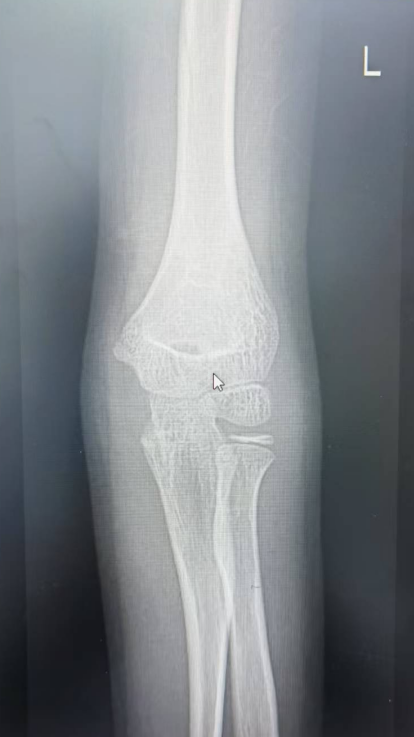

如5岁男童瑞瑞踩着平衡车从广场边缘台阶上摔下,导致左臂肱骨髁上骨折;6岁女童萱萱骑滑板车避让障碍物失去平衡,重重摔倒,造成胫骨骨折。

桡骨远端骨折,通过手法复位